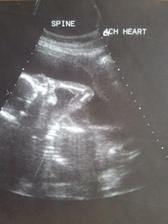

Velký UZ máme za sebou, dopadl dobře i když ještě za 14 dní jdeme na kontrolu, nevim proč, asi nebylo vše přehledné protože malej Kubík těsně před UZ usnul. Ještě nás pan Dr. poslal na doplnění UZ srdíčka. Jinak pěkně nám roste bříško, těhu probíhá bez problémů. Už máme pohyby od 28.6.2010 - to byly jen slaboučké a nevěděla jsem co to přesně je, ale 9.7.2010 mě poprvé Kubík lehounce kopl, teď už jsou pohyby pravidelný každý den, pěkně se mi vlní v bříšku. Tatínek taky zachtil jeden kopaneček 🙂

Tak kontrolu velkého UZ máme za sebou, dopadl dobře, nemáme žádné hrubé VVV. Na UZ srdíčka jsme už také byli, opět jdeme na další kontrolu 5.8.10, protože pan Dr. špatně viděl rozdělení obou komor...to neznamená, že by bylo něco špatně, ale Kubík nechtěl spolupracovat. Jinak vše ostatní je v pořádku a čekáme zdravého chlapečka. Výbavičku už také pomalu máme připravenu, už máme vybraný kočárek, postýlku ... už jen objednat. Rozhodli jsme se, že vše nakoupíme přes internet..... ebutik se ukázal jako spolehlivý el.obchod. Kočárek si koupíme na kocarky-tako

Dnešní kontrola srdíčka v UL dopadla dobře, čekáme zdravého chlapečka. Dnes přes ebutik objednána postýlka, komplet sada na postýlku, přebalovací podložka....a samozřejmě různé drobné zbytečnosti jak by řekl tatínek, ale maminka chce aby se malej Kubík měl jak v bavlnce 🙂